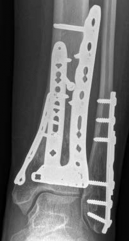

Fig 2.2-6a–b Immediate postoperative x-rays showing restoration of the ankle mortise and distal tibia alignment through anatomical and stable fracture fixation.

1. AP view.

2. Lateral view.